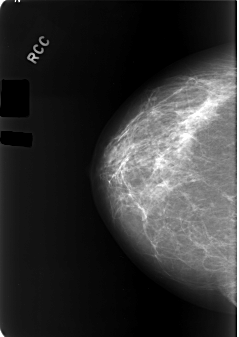

C_0170_1.RIGHT_CC

RIGHT_CC LINES 5720 PIXELS_PER_LINE 4056 BITS_PER_PIXEL 12 RESOLUTION 50 NON_OVERLAY